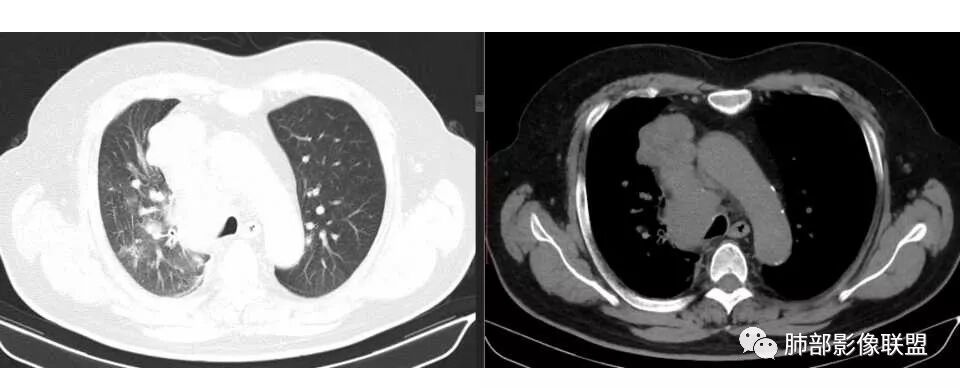

张帅: 患者以肢体无力就诊,既往有吸烟史,胸CT:右肺门占位性病变,密度不均,病灶内病灶内支气管明显狭窄,走行僵硬,病灶边缘光滑,呈浅分叶,未见明显毛刺,对中叶支气管明显挤压。右肺内可见散在片状实变影,前纵隔淋巴结明显肿大,内可见低密度区,2r 4r 7 10r淋巴结明显肿大。诊断考虑恶性方向,肺癌(小细胞)并纵隔肺门淋巴结转移?淋巴瘤?

水晶石头: 患者中老年男性,以四肢乏力为症状表现,有吸烟史。胸部CT:右肺上叶不规则结节,周围见磨玻璃影,小叶间隔增厚。同侧纵膈明显淋巴结肿大。综合考虑恶性。存在小病灶大转移,冰冻纵隔,且有内分泌症状,首先小细胞癌可能大。监测排外淋巴瘤。

阿仙奴: 右上叶结节,形态不规则,右上叶和右中间支气管狭窄,右上管腔内可及结节状物,右肺上叶可见大小不等光滑结节,小叶间隔增厚,纵隔和肺门淋巴结明显肿大。考虑恶性,小细胞?

王秀仙: 右肺门肿块,中间段支气管壁增厚,管腔狭窄,上叶支气管开口截断,周围肺组织可见斑片影及小叶间隔串珠状增厚,纵膈淋巴结肿大并见低密度坏死,考虑鳞癌。鉴别小细胞肺癌

彭君: 右肺上叶多发结节 较大结节周围磨玻璃边缘清 右肺门及纵隔增大淋巴结融合 支气管壁不规整增厚 管腔狭窄但通畅 考虑恶性 肺内病变不像阻塞性炎症 原发的话先考虑淋巴瘤?鉴别小细胞

局限性中央间质增厚,考虑癌性淋巴管炎

部分区域有结节感

1.右肺上叶不规则结节影,右肺门及纵隔多结节并形成巨大块影,密度均匀,沿途支气管明显狭窄。

原发灶小或隐匿,肺门纵隔淋巴结异常增大,所谓“娘小崽大”常见于肺小细胞癌!

2.右肺小叶间隔增厚伴微小结节,提示癌性淋巴管炎。